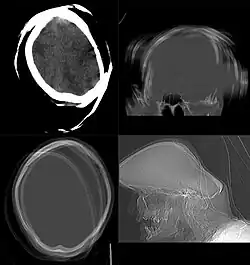

Non-contrast CT

CT procedure in which contrast media is not used is often called as Non-Contrast CT (NCCT) or plain CT. This procedure is employed when there is already a sufficient contrast distinction in the target tissues, rendering the resulting image diagnostically significant. The process involves acquiring a topogram, followed by scanning the region of interest and reconstructing the data, marking the conclusion of the procedure. The non-contrast CT scans are rapid, less hazardous, and cost-effective procedures. Non-contrast CT head scans are useful in the identification of various conditions, encompassing traumatic hemorrhages, subdural hematomas, cerebral edema, fractures, and in detecting foreign bodies, such as tempered glass, in emergency situation.[134]